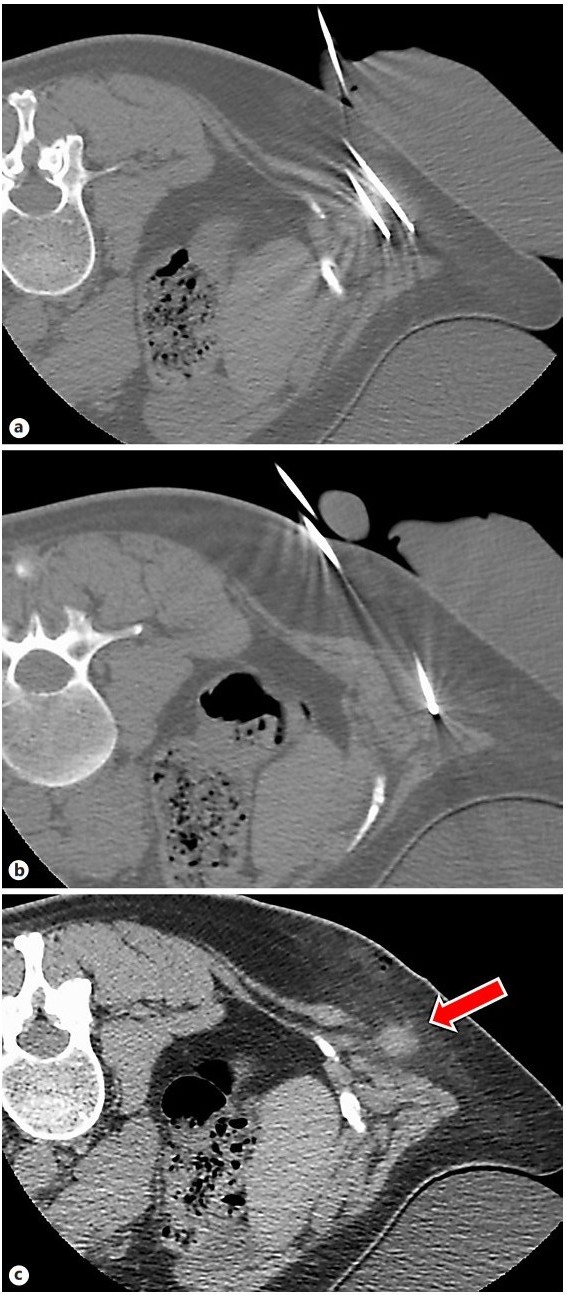

Results: Cryoablation of this mass was successful with no complications. CT images during the procedure demonstrated circumferential coverage of the entire lesion with no injury to the surrounding tissues.